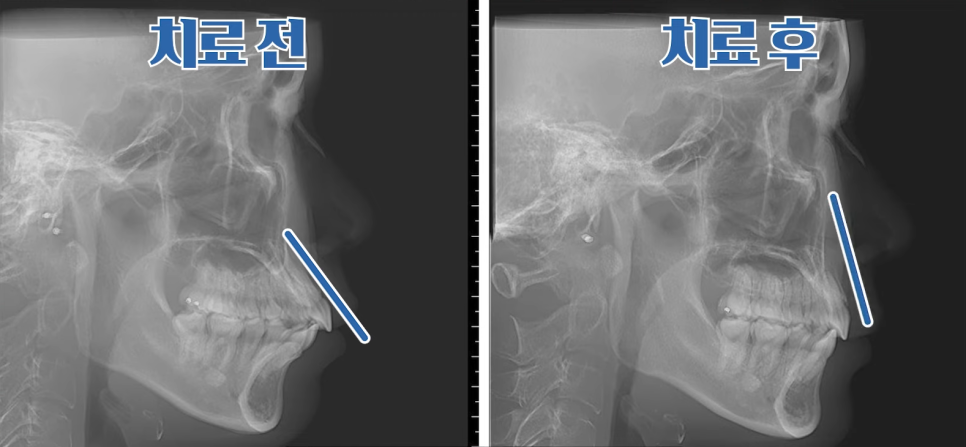

치료 전 X-ray 측면 모습으로도 치아가 앞으로 기울어져 있고,

입이 튀어나온 모습을 확인할 수 있습니다.

상악, 하악 각각 첫 번째 소구치를 발치했고,

인비절라인을 통해 치아를 뒤로 이동시키며 돌출을 점진적으로 개선했습니다.

뻐드러져 있던 치아 배열 모습이 정상적으로 돌아온 걸 확인하실 수 있을 겁니다.

총 치료 기간은 약 20개월이 걸렸는데요.

치료 전후 X-ray 사진을 비교해 보면,

기울어졌던 앞니가 정상 각도로 줄어들었고 자연스레 돌출입도 개선된 걸 볼 수 있지요.